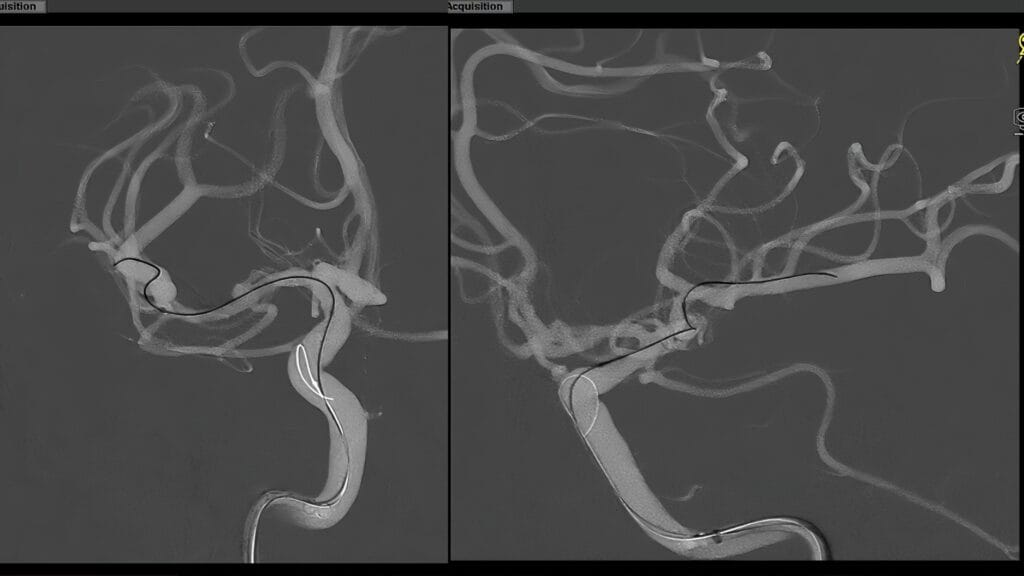

Embolización con coils asistida por stent para aneurisma M1

El Dr. JaeHyun Shim realiza una embolización con coils asistida por stent para tratar un aneurisma no roto de M1 derecho.